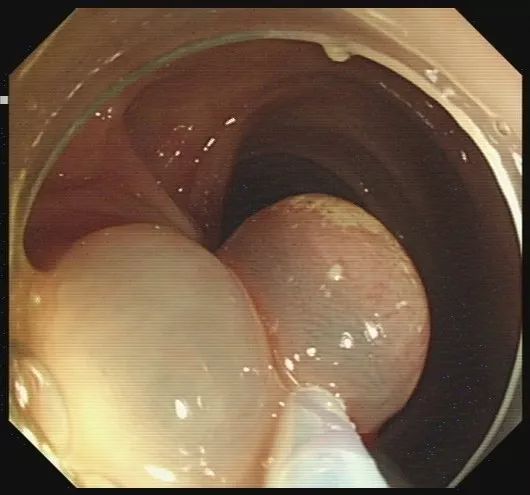

步骤一:发现息肉,并将其暴露于视野正中。

图片